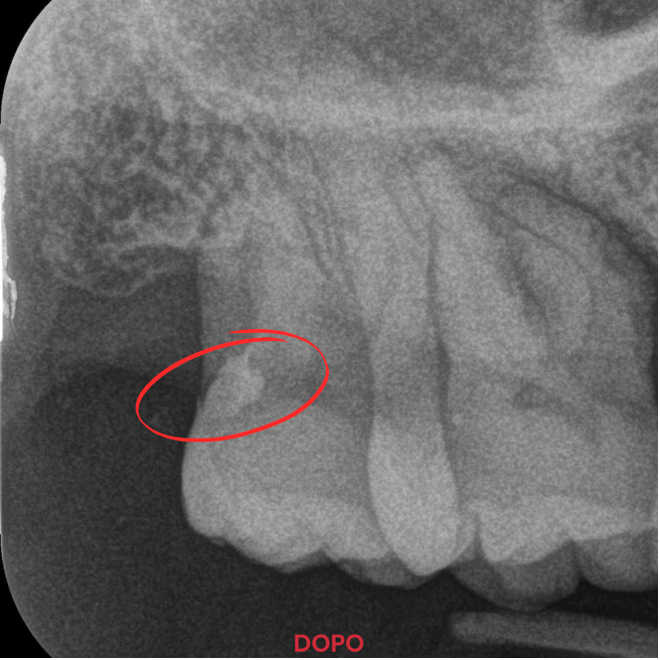

Grazie a Stela, il restauro dell’elemento 1.7 è stato completato con successo senza troppe difficoltà. Ecco i punti chiave del risultato:

- Interfaccia senza Gap per una durata eccezionale.

Ho potuto notare una rapidità di esecuzione, zero gap a livello marginale, estrema lucidabilità e durezza di superficie del restauro ultimato. Stela ha rivoluzionato il mio modo di lavorare!